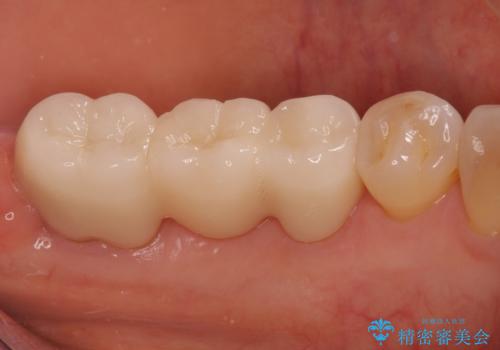

奥歯が割れた インプラントは不向き 部分矯正後、ブリッジで治療

- 63.8万円 左下部分矯正27.5万円 奥歯ブリッジ36.3万円(仮歯1.1万円×3本 ジルコニアクラウン11万円x3本)費用は治療当時の料金となります

奥歯の部分矯正を行うことで、歯の傾きが良くなり、結果神経を取らずにブリッジを入れていくことができました。